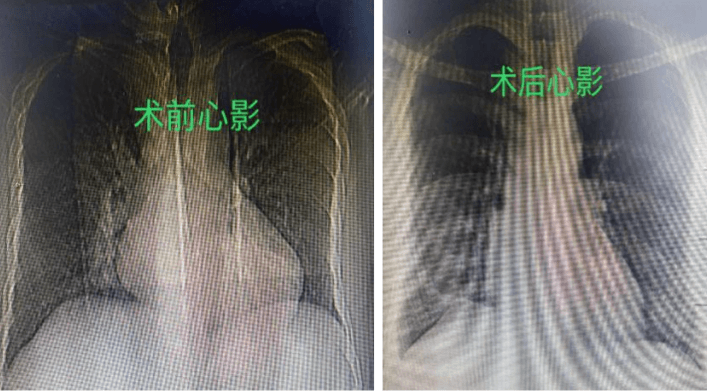

7月25日,在麻醉團隊、體外循環等團隊的保駕護航下,祝恒山主任帶領的手術團隊在張先生的右側腋下切口了一個不到5厘米的小切口,開始為患者實施二尖瓣成形術和房間隔缺損修補術,不到3個小時,手術團隊便順利地為患者的心臟進行了“修補”,術后復查胸片及心臟超聲效果滿意。

該手術的實施,體現了小切口技術的諸多優勢,它減小了傳統開胸救心手術時候入路牽拉和創傷,手術中出血少,術后疤痕小,美觀,患者術后恢復快,對于術后美觀、呼吸功能、運動功能恢復具有顯著優勢,更重要的是,張先生胸廓的完整性能夠得以保留,避免了胸骨愈合并發癥,大大降低了患者對常規開胸的恐懼心理,有利于患者術后早期下床活動,利于術后心臟康復。延安大學咸陽醫院心胸外科為張先生真正實現了“美容切口”的愿望。需要指出的是,小切口心臟手術并不是適合所有心臟病患者,是否能進行小切口手術還需要??漆t生根據患者具體的情況來進行評估。